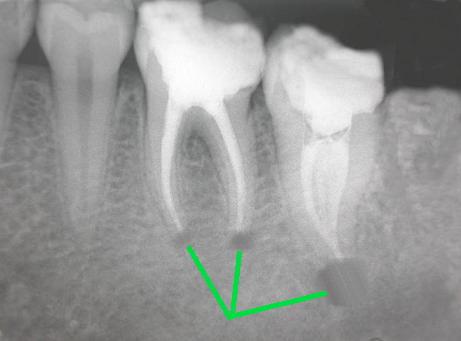

5、牙根尖周炎

如果你突然觉得牙痛的感觉,经常从轻微地慢慢更痛,而且持续的时间也不长,可能就几分钟,不过后来就疼痛的时间变长了,这也许就是牙根尖周炎发作。正常来说,牙根尖周炎患者他们的牙齿受到外界刺激,就会有那种刺痛的感觉,真的无法忍受就要吃点止疼药了,这样能够缓解一下疼痛,有时间去个医院彻底地根治。